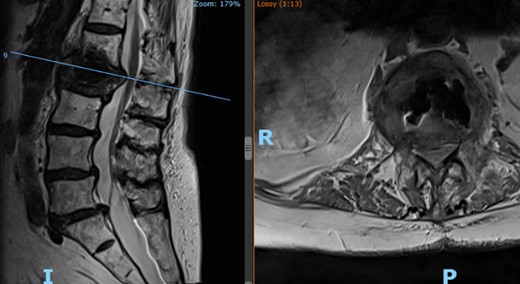

Patient’s lateral (left) and axial (right) MRI following the kyphoplasty procedure, demonstrating L1 fracture with retropulsion and compression of the conus.

Two-week postoperative check revealed the patient was still feeling disabled, with a new onset of burning pain in the right groin and thigh, severe back soreness, numbness, and leg weakness, which were refractory to pain medications. Lumbosacral spine MRI redemonstrated the cemented L2 compression fracture with posterior bony retropulsion, along with progressive collapse of the anterior inferior corner of L1 impacted into the anterior aspect of the cemented L2 compression fracture, associated kyphosis at L2, and multilevel degenerative disk changes (Fig. 3). After an extensive review of possible management options for the patient’s symptoms, the patient elected to undergo an open-approach multilevel PPSF.